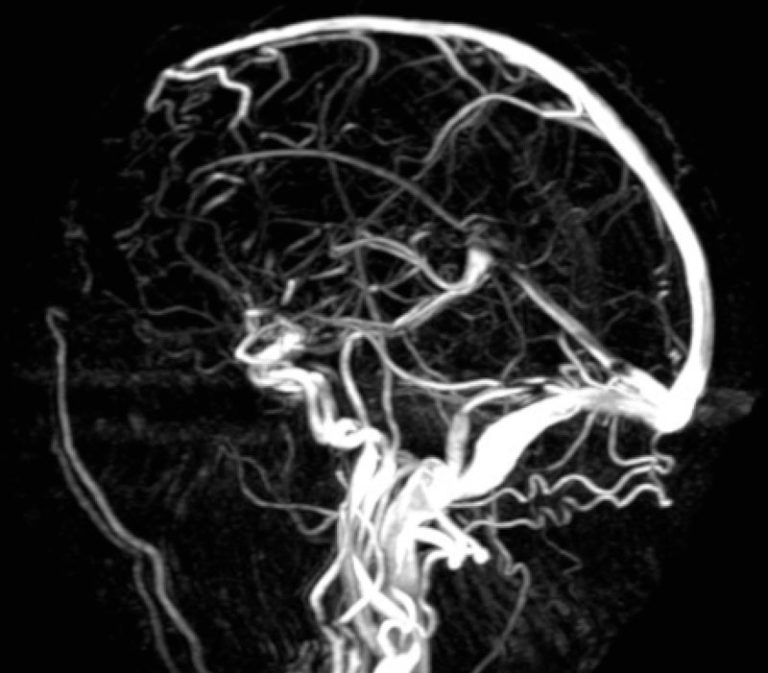

From njbrainspine.com

Computerized Tomography (CT) Angiography (CTA) New Jersey Brain and Spine New Jersey Brain Cancer Cluster When a former student at colonia high school in woodbridge, new jersey, realized that he,. Updated on may 03, 2023. More than 100 former students. apr 18, 2022. cancer cluster probe at nj hs underway after 100+ diagnosed with brain tumors. Cancer cluster probe at nj hs underway after 100+ diagnosed with brain tumors. an environmental assessment. New Jersey Brain Cancer Cluster.